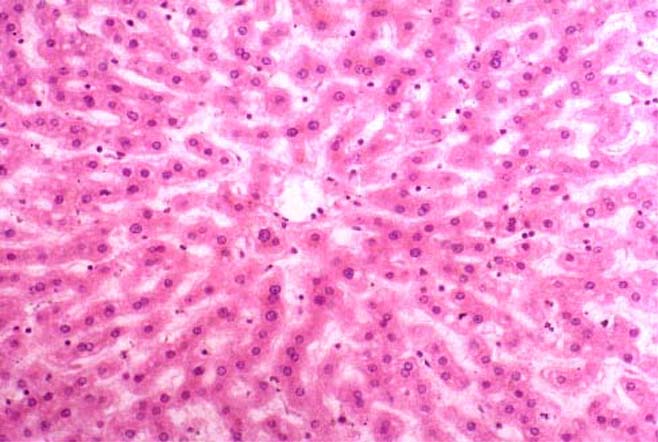

溶组织阿米巴原虫在其生活史中出现滋养体及包囊期两种不同形态。包囊被人食入后,可无损地通过胃及小肠上段,到小肠下段经胰蛋白酶消化,具有4个核的成熟包囊,可脱囊而出成为小滋养体(直径7~20µm),寄生在肠腔中,以细菌为食物,不损伤肠壁组织,二均分裂繁殖,在缺氧的回盲部生长良好。在机体抵抗力不足或局部肠黏膜有损伤时,小滋养体可变为大滋养体(直径20~40µm),能分泌溶组织酶破坏肠壁组织,侵入肠黏膜及黏膜下层,大量繁殖,形成局限性黏膜下脓肿,内容主要为坏死性物质,脓肿破裂,形成烧瓶样溃疡。溃疡与溃疡之间的黏膜基本正常,这一点与细菌性痢疾显然不同。当机体抵抗力增强时,大滋养体可变为小滋养体,并可进一步变为包囊(直径10µm左右),随粪便排出体外。在凉爽潮湿的环境中可生存2~4周,冰箱中可生活6~7周,但不耐热,50℃ 5min即死亡。只有4个核的成熟包囊,才有传染性,1~2个核的未成熟包囊无传染性,但在合适的外界环境中,可以发育成4个核的包囊。大小滋养体如排出体外,均很快死亡。如病程拖久,肠壁组织的破坏和结缔组织增生同时进行,可致肠壁肥厚,肠腔狭窄,偶可因结缔组织过度增生而形成“阿米巴瘤”。